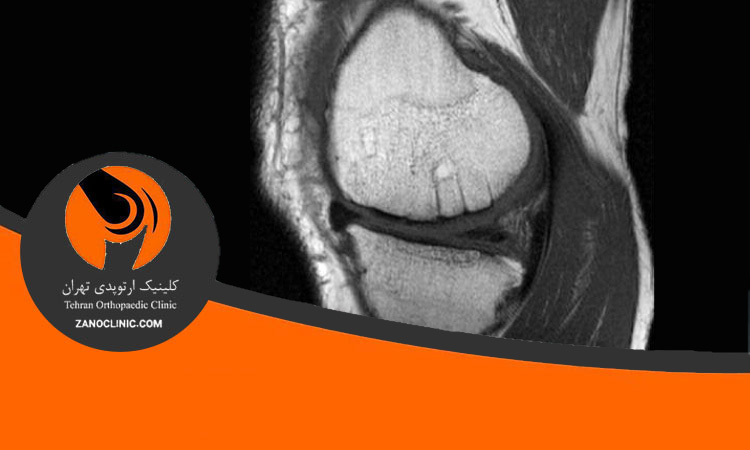

ترمیم رباط صلیبی

ترمیم مینسک و رباط صلیبی PCL و درمان اولیه آن

کلینیک ارتوپدی زانو کلینیک با ارائه انواع خدمات جراحی زانو اعم از تعویض مفصل زانو و لگن، بازسازی مینسک و رباط صلیبی PC، جراحی غیر تهاجمی ACL به صورت آرتروسکوپیک و … با جدید ترین متدهای دنیا و پیشرفته ترین تجهیزات پزشکی، در حال خدمت به شما عزیزان می باشد.